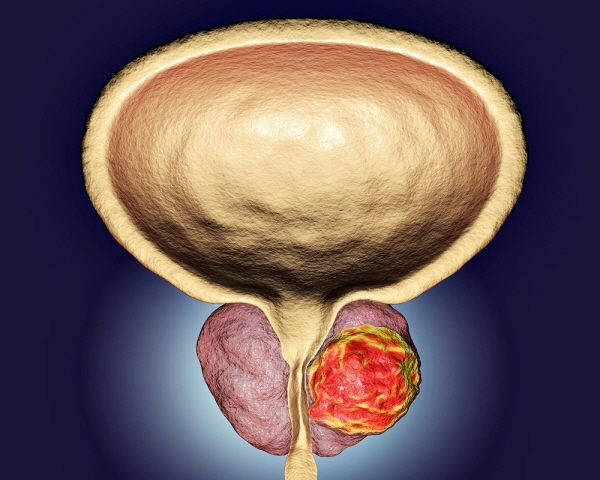

전립선암은 전립선에 암세포가 발생하는 질환입니다. 전립선의 일부 세포가 정상 세포의 성장을 조절하는 능력을 상실하고 통제할 수 없을 정도로 성장하여 악성 종양이 되는 질환입니다. 일반적으로 전립선암은 주로 전립선 상피 세포에서 발생하는 선암으로, 약 70~80%가 전립선 말초 부위에서 발생합니다.

전립선암 치료에는 호르몬 치료, 수술 치료, 방사선 치료, 화학 요법의 네 가지 주요 유형이 있습니다. 전립선암은 남성호르몬의 영향을 많이 받기 때문에 남성호르몬의 생성을 차단하고 전립선에 작용하지 못하게 함으로써 전립선암을 예방할 수 있습니다. 수술적 치료는 전립선 내의 암세포를 직접 제거하는 방법이며, 수술 방법이 너무 강할 경우 고에너지 방사선을 사용하여 암세포를 죽일 수 있습니다.